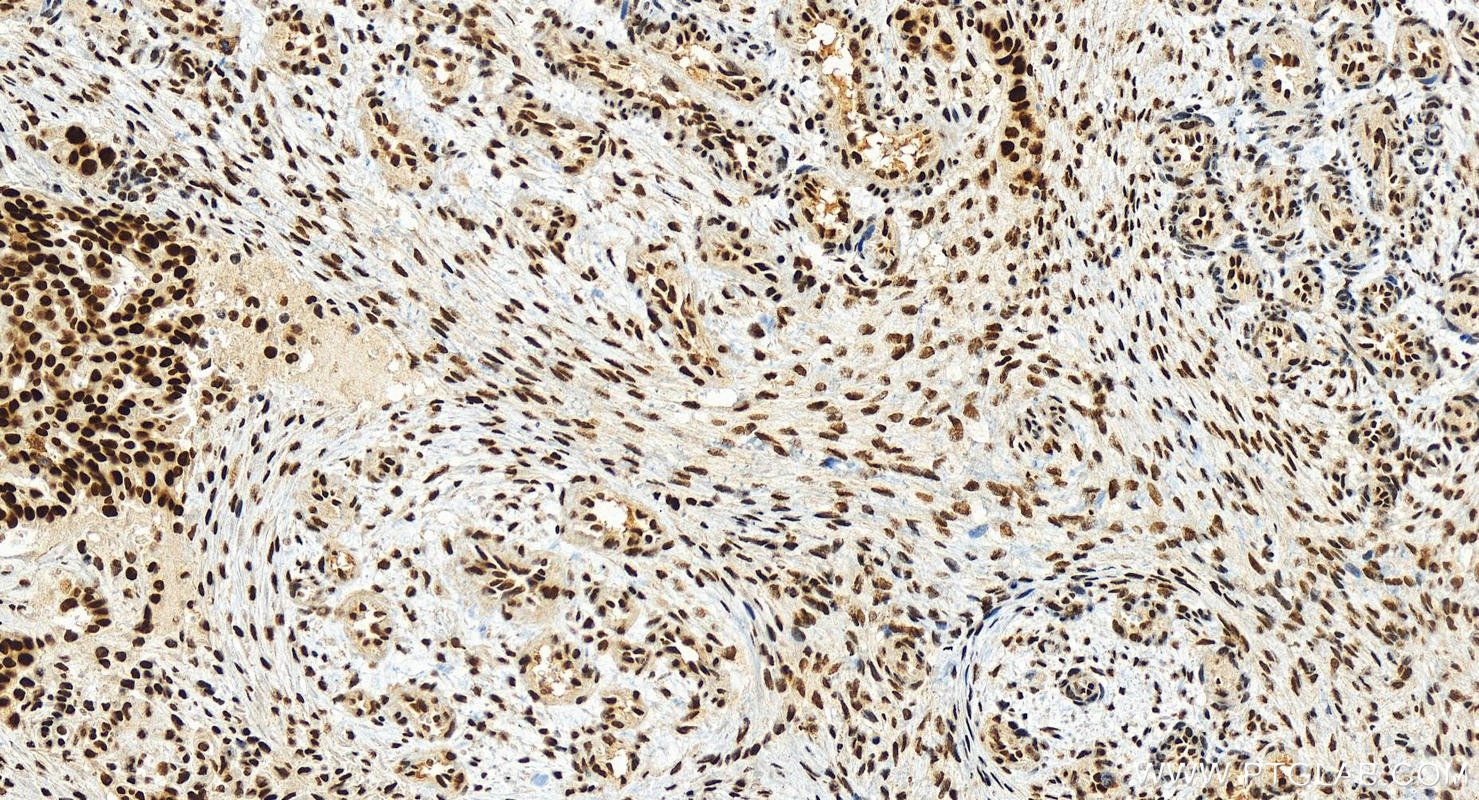

| Positive IHC detected in | human ovarian cancer Note: suggested antigen retrieval with TE buffer pH 9.0; (*) Alternatively, antigen retrieval may be performed with citrate buffer pH 6.0 |

| Immunohistochemistry (IHC) | IHC : 1:500-1:2000 |